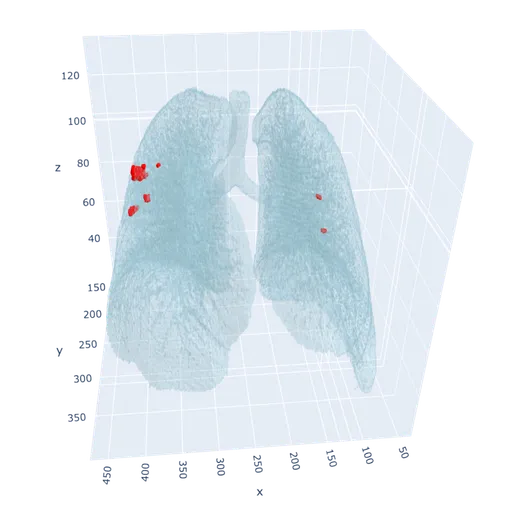

Lung Nodule Detection and Tracing Across Scans

Obvios.ai utilizes cutting-edge artificial intelligence to meticulously detect and track lung nodules, facilitating swift and precise diagnostics, thereby ensuring superior care and timely intervention for patients.